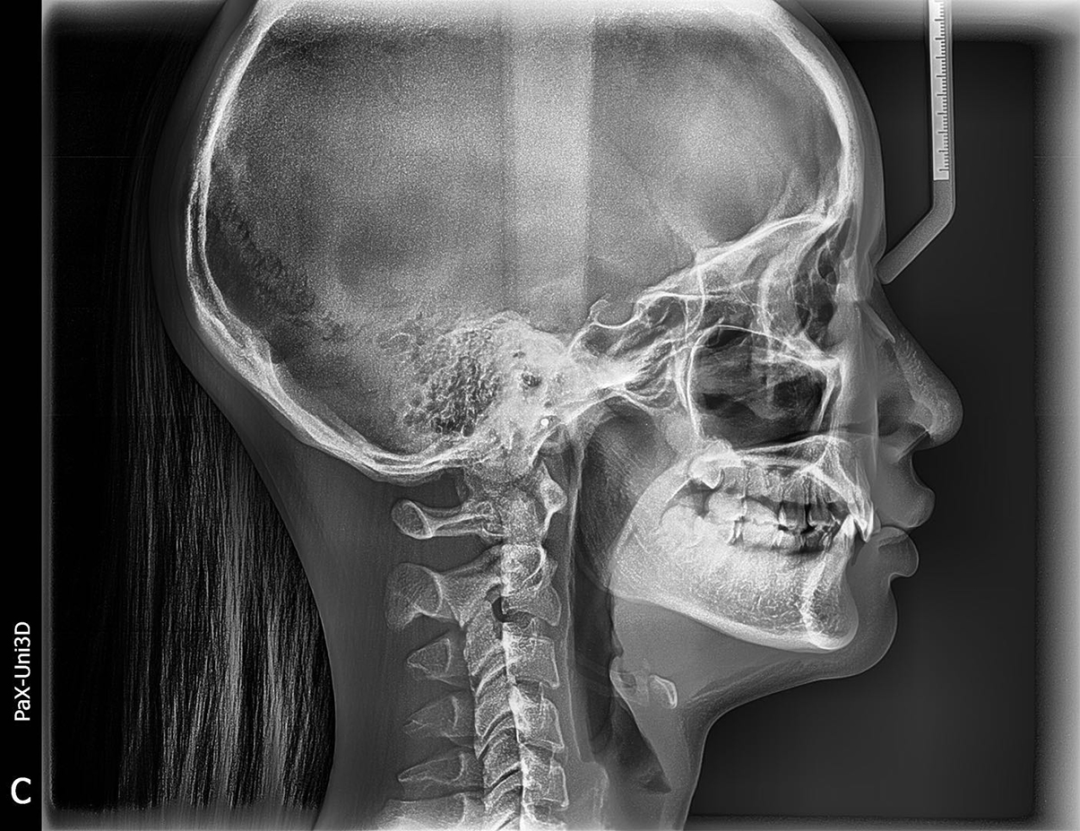

通过牙片资料可以看到女士是闭锁性深覆合,上牙几乎把下牙完全盖住,整个咬合关系并不是很理想,从侧貌看,她的下嘴唇相对靠后,下巴有点后缩,颏唇沟很深。